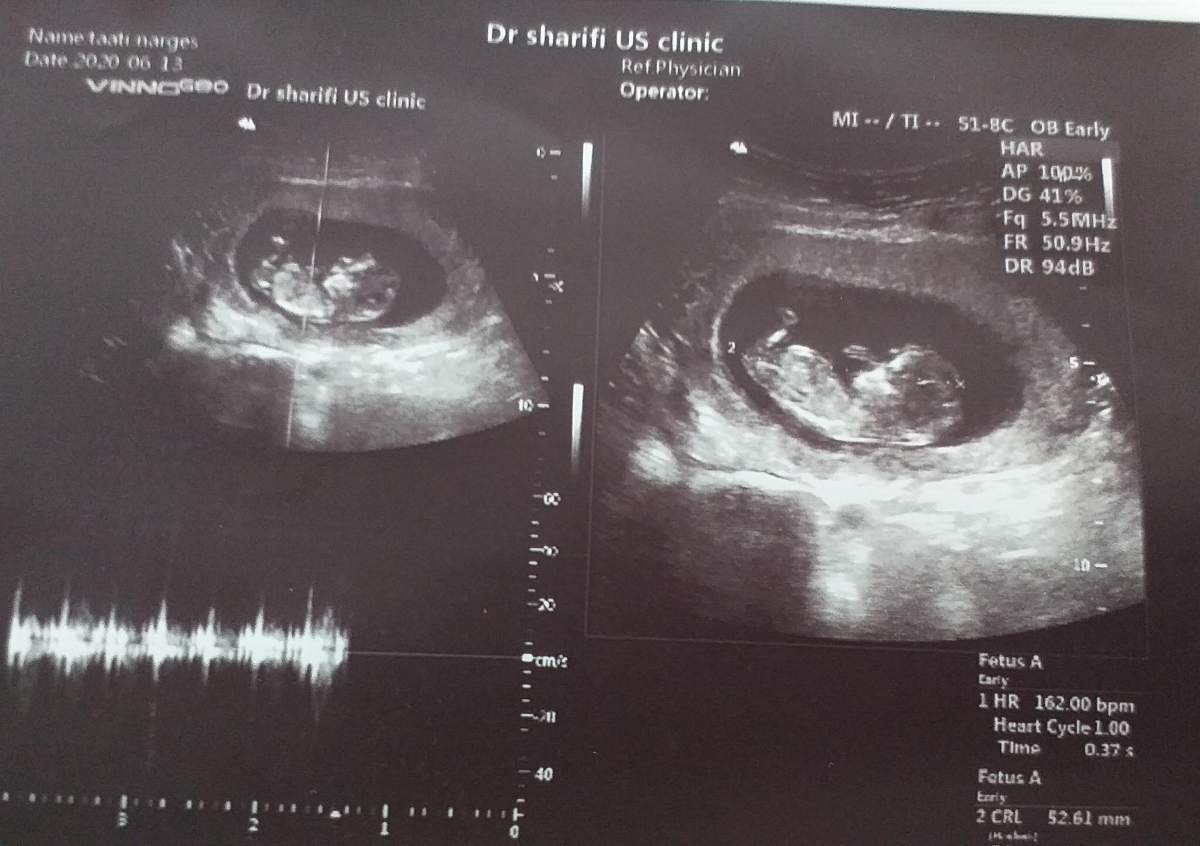

سلام خانوما، سونوی ان تی من رو ببینید 🤰🏻

دختره یا پسر 😊

سونوی ان تی وحدس جنسیت